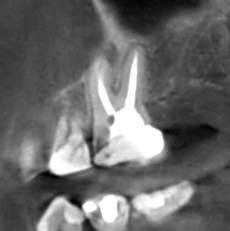

Александр В.В. Опубликовано 29 марта, 2023 Поделиться Опубликовано 29 марта, 2023 (изменено) Здравствуйте! Уже давно на шестом верхнем зубе есть гранулёма или киста размером 5-6 мм. Несколько лет назад пробовали класть кальций в каком-то виде, но, видимо, не помогло. Сейчас всё-таки решил перелечить этот канал, но эндодонтист сказал, что это только часть дела и надо делать все каналы. Кроме того, как я понял, проблема не в том канале, который запломбирован, а в том, который проходит рядом с ним и не был обнаружен и запломбирован. На этом снимке это верхний левый корень и в его правой части темное пятно - это вроде и есть тот ненайденный канал. Здесь видна гранулёма и запломбированный канал (корень слева). А здесь справа от запломбированного канала (левого корня), тот самый незапломбированный. Но у меня есть сомнения по поводу такого вывода, потому что в других каналах можно обнаружить более очевидные "темные каналы" в зависимости от среза. На этих снимках обращаю ваше внимание на правый канал. Если нужно, могу предоставить другие проекции, потому что имею диск с данными КЛКТ. Вопросы. 1. Действительно ли на снимке ненайденный канал на корне зуба с гранулёмой? 2. Возможно ли перелечивание одного канала с гранулёмой или кистой или нужно распломбировать сразу все каналы во всех корнях? 3. Если на снимке всё-таки ненайденный канал, то не кажется ли вам, что он прямой, а не изогнутый? Если прямой, его может обработать терапевт без использования микроскопа? Изменено 29 марта, 2023 пользователем Александр В.В. Ссылка на комментарий